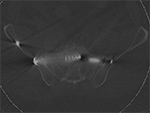

Bone (or “detail”) filters use a very sharp image filter, which accentuate fine spatial details, including image noise and artifact. Since musculoskeletal CT images are typically reviewed using “bone” windows (window 2000 HU, level 500 HU) these fine artifacts may be obscured and overlooked (Figure 4). In the presence of metallic hardware, these artifacts occur to a much greater extent and can result in degraded image quality. In the setting of metallic implants, it is helpful to use a soft image reconstruction, such as the standard filter used for general abdominal imaging, and even softer filters can be considered in the setting of highly attenuating implants, such as cobalt or steel, or if there is concern for soft tissue abnormality adjacent to hardware (Buckwalter, 2011). Evaluation of fine hardware in a small region of interest, such as a scaphoid fracture, offers an exception to this rule where a sharp bone algorithm may be beneficial (Ohashi, 2009).